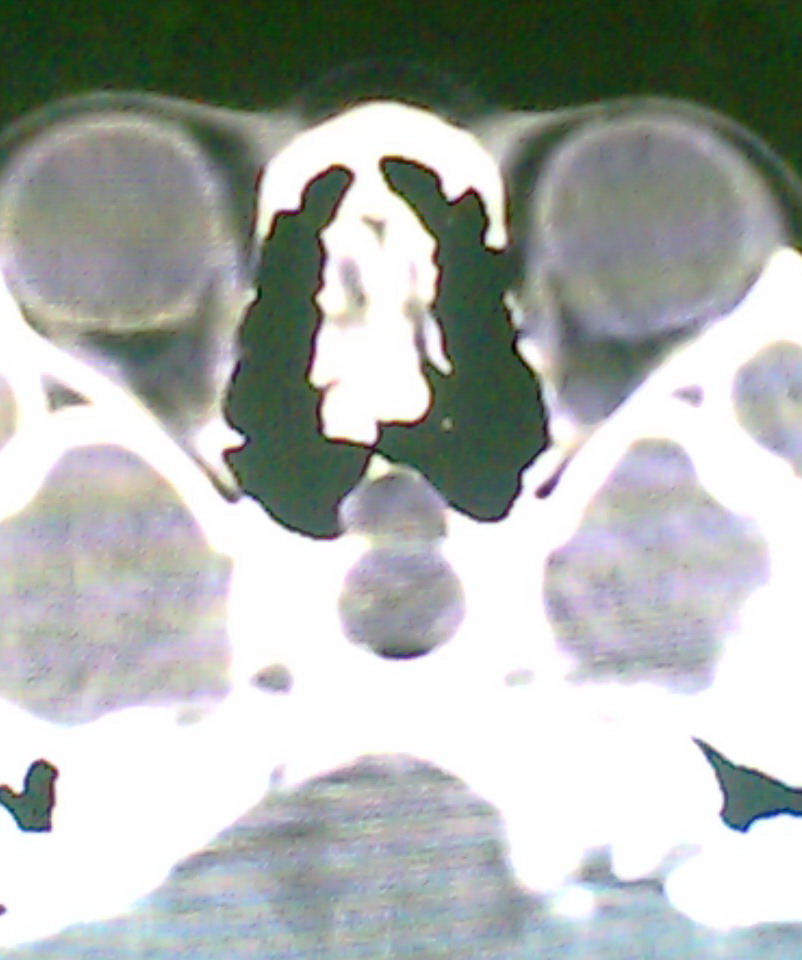

女、18岁,身高1.5左右,鼻塞、流涕数月,两侧瞳孔明显增大,曾与几年前去北京看眼,未发现病变。

考虑起源与蝶窦的粘液囊肿。

考虑脑膜脑脊液鼻内膨出

考虑起源于蝶窦的粘液囊肿突入鼻咽部。

\"几年前去北京看眼\"不知这句话有何玄机,支持考虑脑膜脑脊液鼻内膨出,膨出口在蝶鞍处

建议冠状面扫描,支持:脑膜鼻内膨出; 蝶窦粘液囊肿突入鼻腔可能性小。

在上级医院冠状位ct扫描后,诊断为:脑膜膨出,已住院准备手术。等待术后结果。